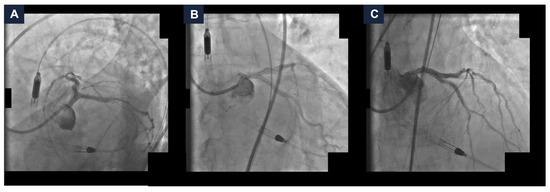

The final angiographic result was satisfactory, with a Thrombolysis in Myocardial Infarction (TIMI) grade 3 flow (Figure 3 and Video S2). The hemodynamics remained stable, so the MCS device was removed at the end of the procedure, with no vascular access complications. A total of 40 mL of Iodixanol 270 mg I/mL was administered. Post-procedurally, the eGFR reached 13 mL/min/1.73 m2. The patient was managed with intravenous hydration. The serum potassium did not exceed 5.0 mEq/L and the urine output remained stable. After a few days, the kidney function returned to baseline values (eGFR 27 mL/min/1.73 m2). No in-hospital adverse events occurred. The patient remained free from angina at the one-year follow-up [6].

Figure 3.

Final complex high-risk indicated procedure result. Final coronary angiography demonstrating a good final result with Thrombolysis In Myocardial Infarction grade 3 flow in spider (panel A), caudal (panel B), and cranial (panel C) views.